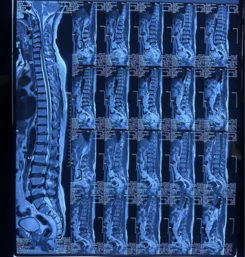

Before & After Clinical Gallery

We showcase real patient cases (with consent), including:

• Pre- and Post-operative MRIs and X-rays

• Disc Herniations, Stenosis, and Spondylolisthesis cases

• Visible improvement in alignment and decompression

• MRI showing nerve or spinal cord compression